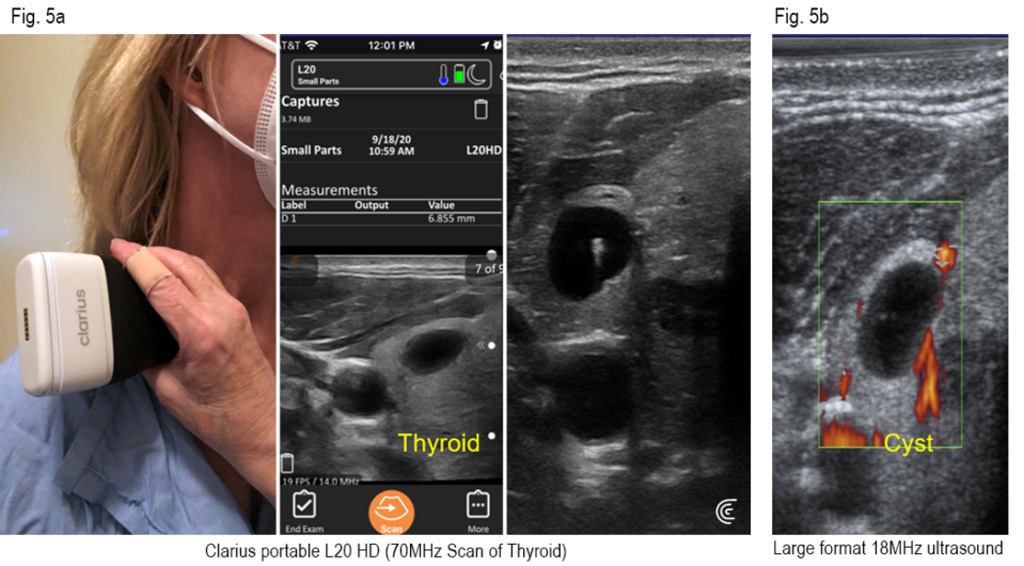

Thyroid

This scan can be done in a larger study – you can see the Clarius device (Fig. 5a) and the L20 preset for small organs. The Thyroid is labelled (yellow) as the dark cyst. (Fig. 5b) The 18 MHz probe of our large unit also shows the thyroid simple cyst and this is compared with a study with a 70 MHz probe of the Clarius showing the cyst, but with some tiny white echoes of early calcification. The color represents blood flow from the Doppler setting – which we use just to make sure it’s a cyst. For the purposes of this test, we did not turn on the DOPPLER setting on the Clarius, but it is equipped with this feature also.